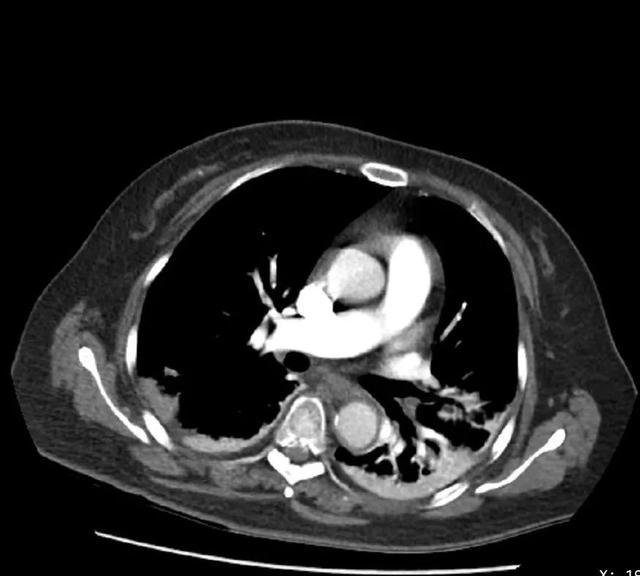

CT检查提示右肺下动脉栓塞,延伸到右肺动脉干

该病例的

复查随访

可见原有的大块血栓完全消失